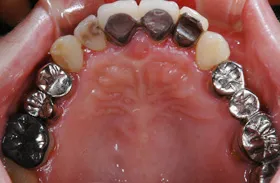

金属を白くし、歯茎の黒ズミを改善したケース

■治療前

■治療後

| 主訴 | 全体的に白い歯にして見た目をきれいにしたい 歯茎が黒くなっているのが気になる、歯ならびも良くしたい |

|---|---|

| 治療方法 | 矯正治療+歯茎の黒ずみの改善+補綴治療 |

| 治療期間 | 3年 |

| 通院回数等 | 約40回 |

| 費用 | 約350万円 |

| リスク・副作用 | 矯正治療も行ったので治療期間が長くなった |